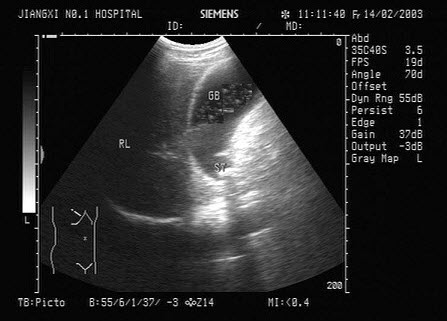

E.本病出现症状愈早,预后愈差;晚期症状为高血压、肾功能减退

68、单项选择题

女,38岁,上腹部经常疼痛,加重2天。声像图如图所示,诊断为()

A.左肝内胆管多发性结石

B.左肝血管瘤

C.左肝钙化灶

D.左肝内胆管蛔虫

E.左肝内胆管积气